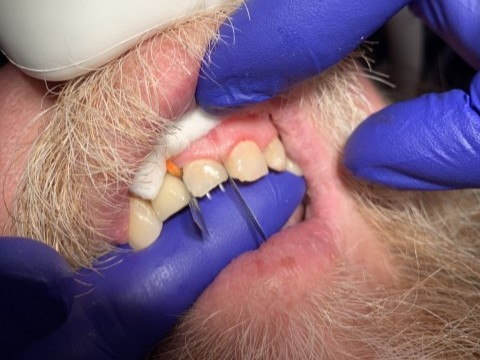

DentXpinTM – placed April, 12, 2012 and still holding strong.

1

DentXpinTM repair.